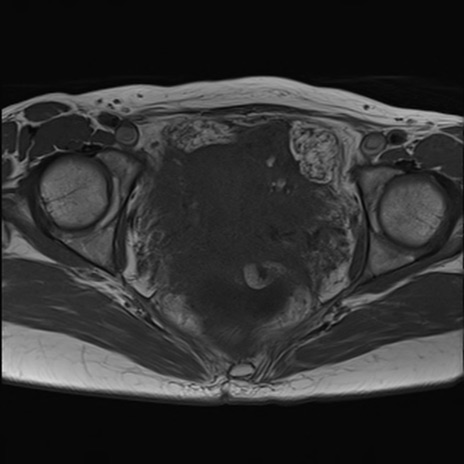

症例39 T1WI(横断像)

MRI(4日後)